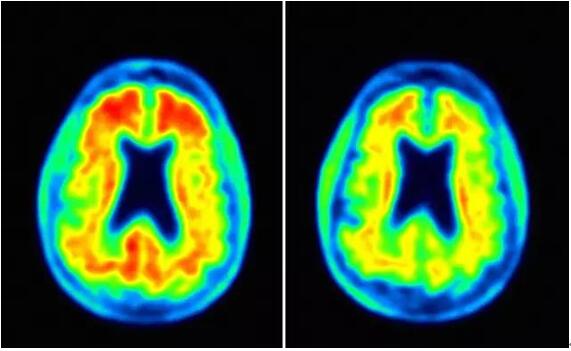

Aducanumab治疗(右)可减少淀粉样蛋白斑块(图片来源:Fortune

1b期研究包括了体重每公斤1毫克(n=31)、3毫克(n=33)、6毫克(n=30)和10毫克(n=32)的固定剂量组;滴定方案组(n=23)和合并的安慰剂组(n=48)。该研究还包括了完成研究一年后安慰剂对照部分患者的长期延长研究(LTE)。在CTAD会议上公布的aducanumab相关数据与先前该研究的结果分析一致。在54周时,相对于安慰剂组,所有固定剂量组中观察到了淀粉样蛋白斑块统计学上的显着减少:1mg/kg[-0.050p<0.05]3mg/kg [-0.130p<0.001]6mg/kg [-0.206p <0.001]10mg/kg [-0.263p <0.001]和滴定组[-0.171p<0.001]